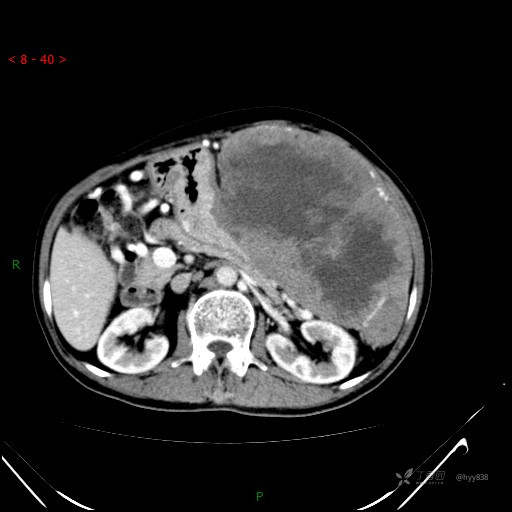

腹部CT平扫

增强动脉期

是病灶太恶、还是患者能忍,腹腔超巨肿物,请会诊---结果公布~

主诉: 左上腹间断疼痛不适近1周

简要病史: 患者1周前出现左上腹间断疼痛,为钝痛,伴左肩部放射痛,无头晕、头痛,无恶心、呕吐、呕血,无便血等不适。为求进一步诊治,门诊以“腹部肿物”收入我科。